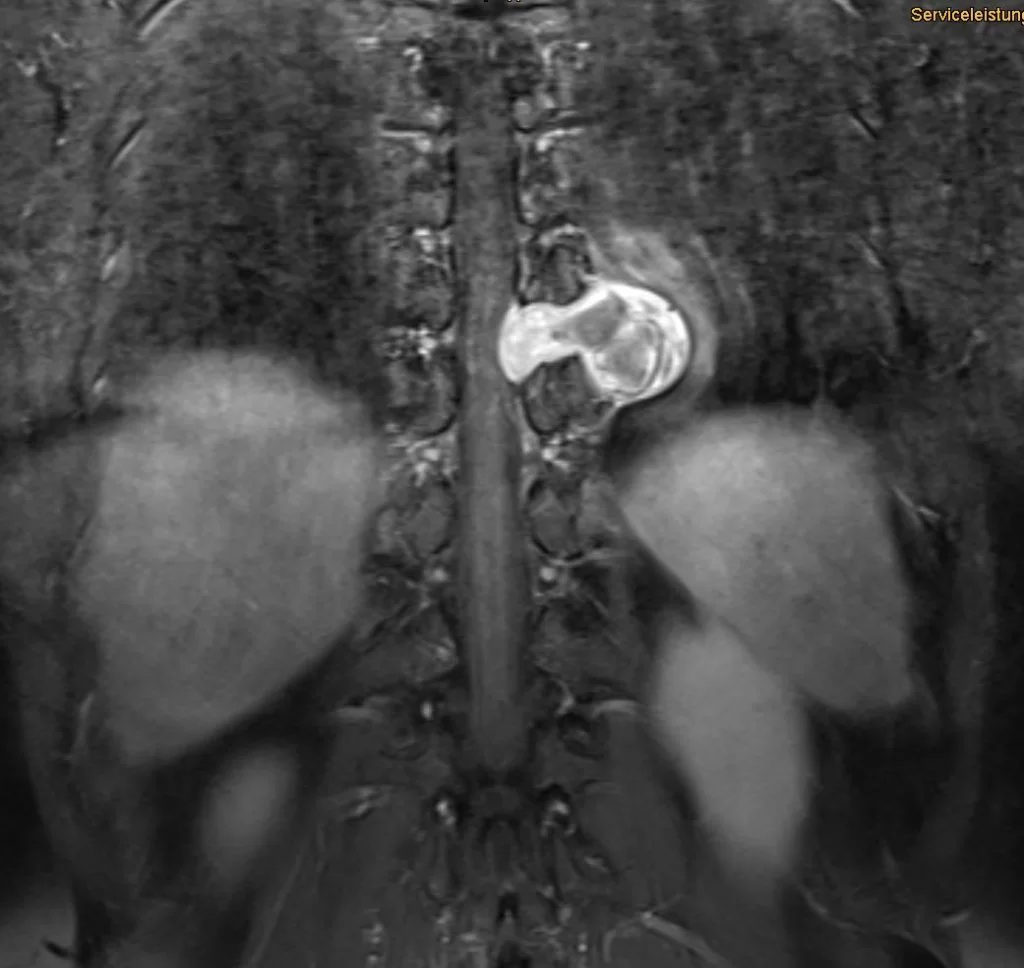

Ο απεικονιστικός έλεγχος με μαγνητική τομογραφία ανέδειξε ευμεγέθη ενδο/εξωκαναλική χωροκατακτητική εξεργασία στο ύψος Θ9/10 αριστερά, ύποπτη για σβάννωμα.

Το συγκεκριμένο σβάννωμα παρουσίαζε σημαντικό εξωκαναλικό κομμάτι (δηλαδή όγκο με επέκταση πέρα απο τη σπονδυλική στήλη και το νωτιαίο μυελό), με πίεση του αριστερού πνεύμονα αλλά και στενή γειτνίαση με τα μεγάλα αγγεία του θώρακα. Παρόλα αυτά, όπως φαίνεται και από την μετεγχειρητική μαγνητική τομογραφία ο όγκος αφαιρέθηκε ολικά, χρησιμοποιώντας μόνο οπίσθια προσπέλαση.